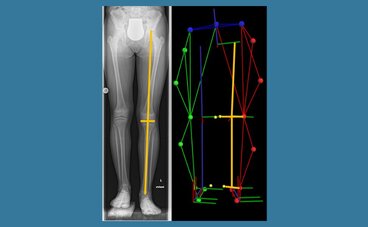

Die Forschungsschwerpunkte umfassen die Analyse und Optimierung der Ganganalyse bei orthopädischen und neurologischen Erkrankungen, insbesondere bei Kindern mit Zerebralparese, idiopathischen Knicksenkfüßen, Achsfehlstellungen der unteren Extremitäten und der Wirbelsäule.

Dabei stehen die Bewertung und Behandlung von Gangabweichungen durch chirurgische Eingriffe, Orthesen und Rehabilitationstechniken im Fokus, ergänzt durch den Einsatz von 3D-Bewegungserfassung und dynamischer Analyse zur Diagnostik und Therapieoptimierung, insbesondere unter Berücksichtigung des Wachstums.